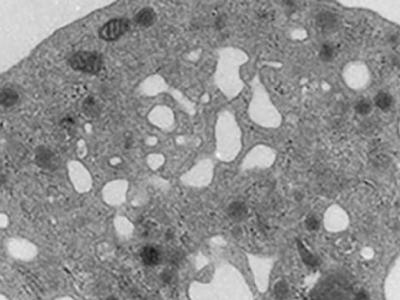

Alysson Muotri的实验室生长了这些由人类干细胞培育而来的大脑...